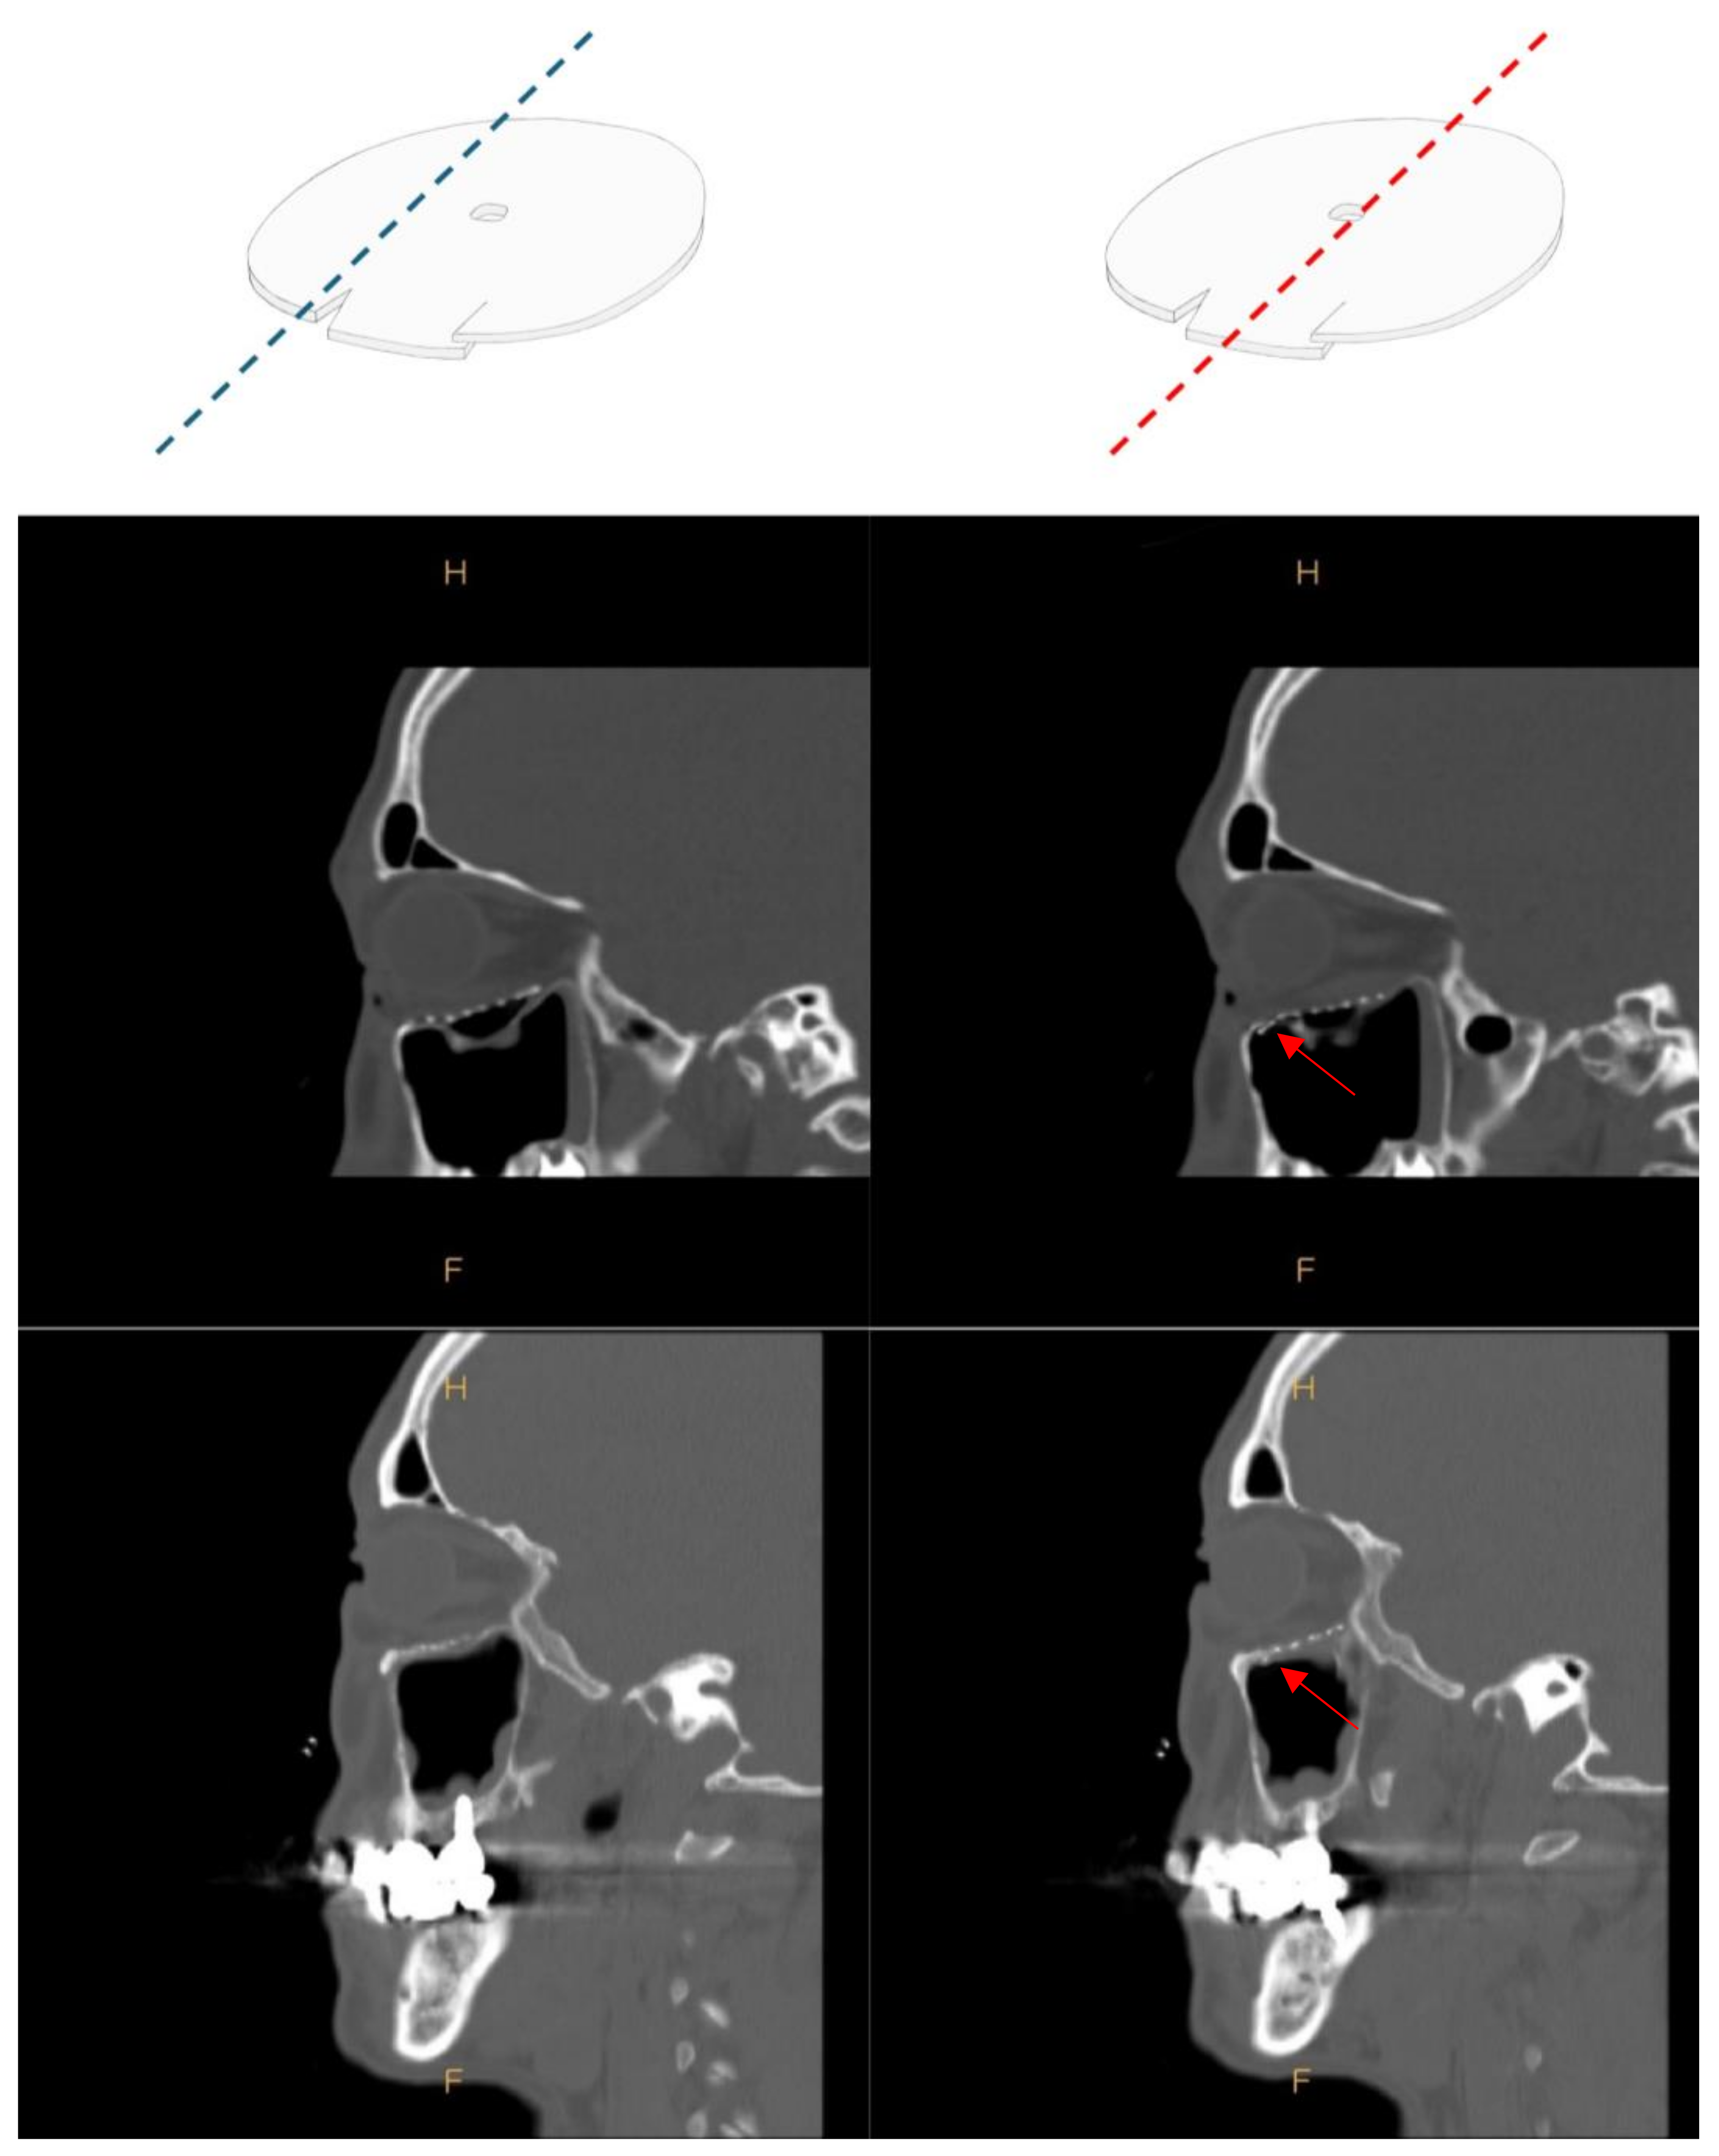

2.2. Surgical Procedure